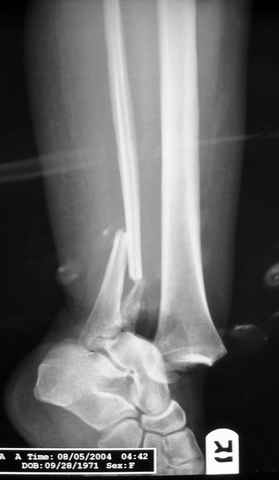

ANKLE FRACTURE

Dear all,40 y.o. man had sustained this terrible fracture falling from a motorbike.

Closed fracture.

This is really Pilon Fx (C3.3; the high energy and the extent of distal tibia comminution are defining it).